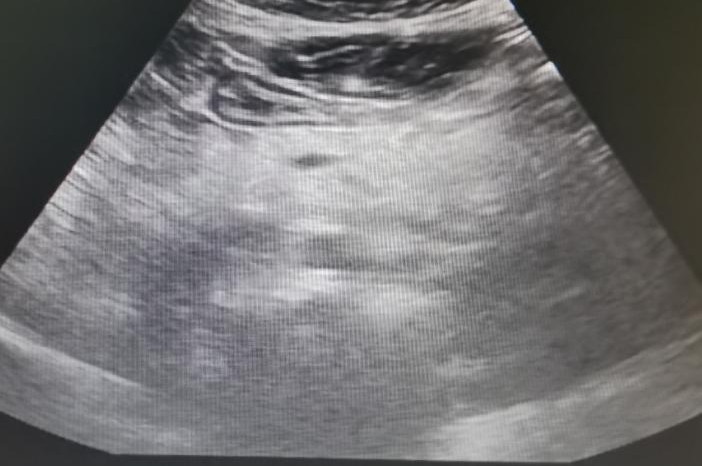

腹部超声(2024年4月11日):肝脏多发实性结节。

腹部超声(2024年4月11日)